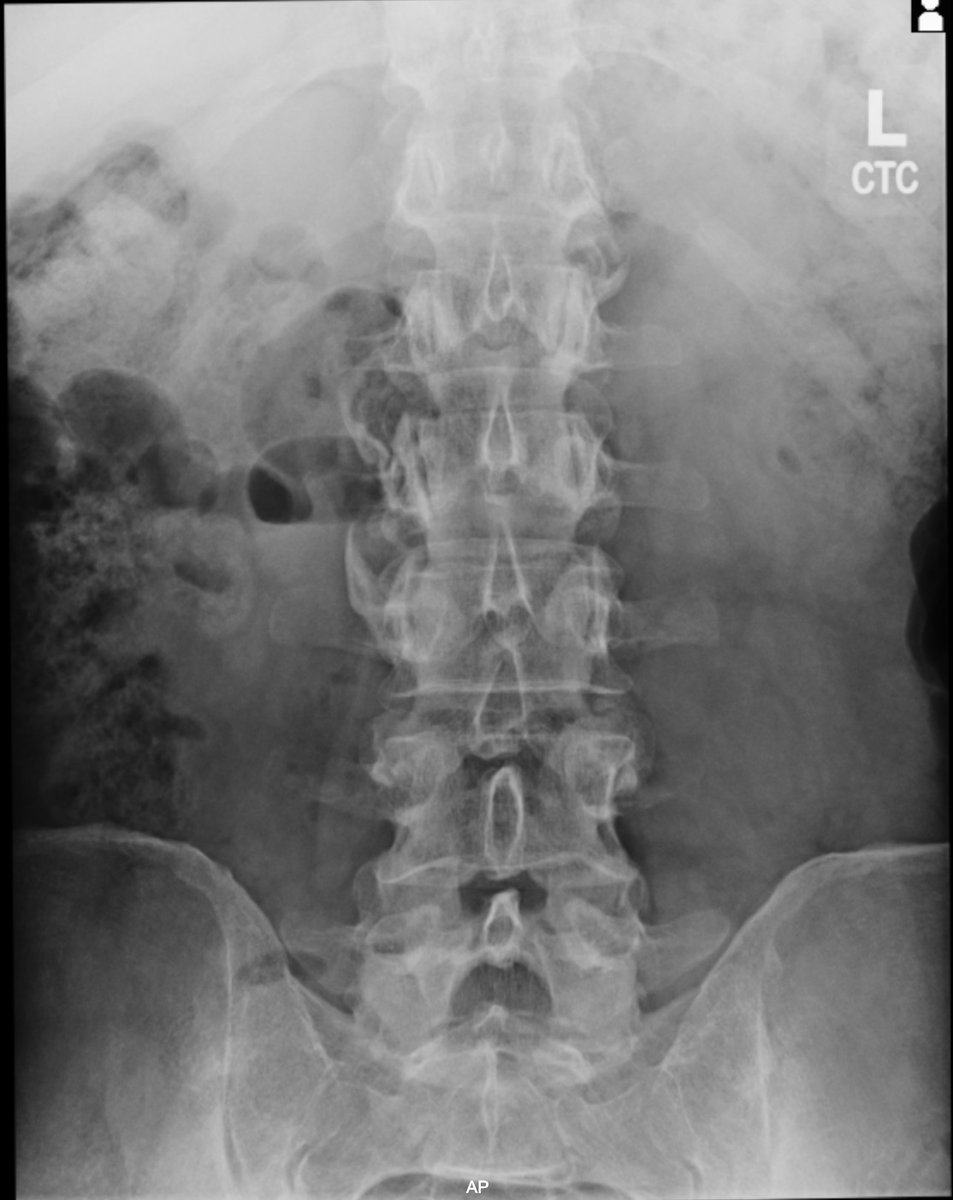

No differences in prevalences of pubic-related radiographic findings between football players with and without groin pain! Great to see another online paper from my PhD🤩 It is open access! 🆓 ⬇️ onlinelibrary.wiley.com/journal/160008… @SORC_C